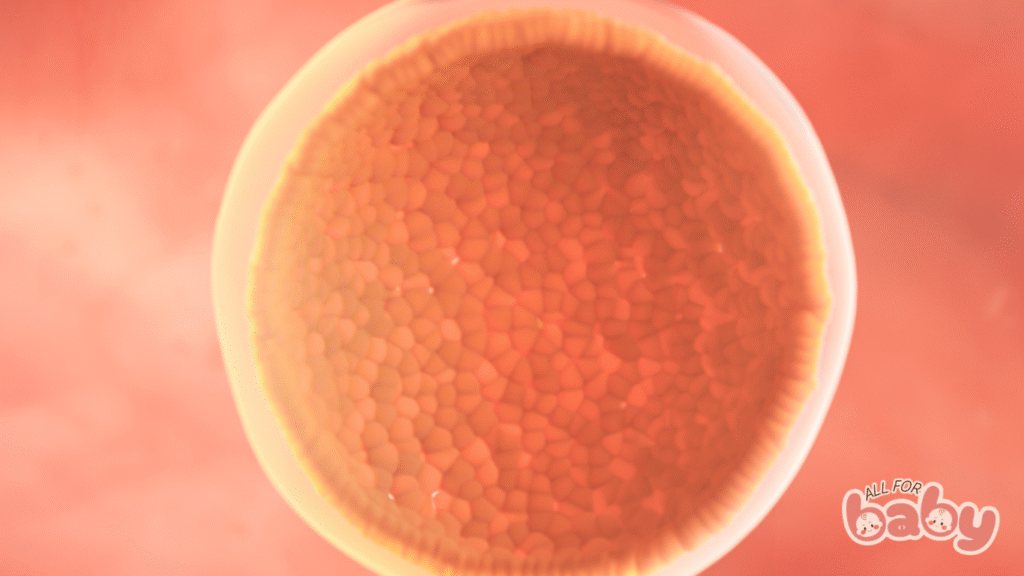

Ở tuần 3, tức là khoảng 1 tuần sau khi thụ tinh, bé của mẹ thực sự bắt đầu hành trình:

Bé lúc này chỉ là một quả cầu nhỏ xíu (gọi là phôi nang – blastocyst) gồm vài trăm tế bào.

Các tế bào bên trong sẽ phát triển thành phôi thai, còn lớp ngoài hình thành nhau thai – nơi cung cấp oxy và dưỡng chất cho bé trong suốt thai kỳ.

Phôi thai đang di chuyển qua ống dẫn trứng để đến làm tổ trong tử cung – một bước cực kỳ quan trọng quyết định sự phát triển của thai sau này.